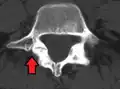

Anterolisthesis L5/S1 -

Anterolisthesis L5/S1. Blue arrow normal pars interarticularis. Red arrow is a break in pars interarticularis. -

Anterolisthesis L5/S1

Isthmic anterolisthesis is where there is a defect in the pars interarticularis (spondylolysis).[15] It is the most common form of spondylolisthesis; also called spondylolytic spondylolisthesis, it occurs with a reported prevalence of 5–7 percent in the US population. A slip or fracture of the intravertebral joint is usually acquired between the ages of 6 and 16 years, but remains unnoticed until adulthood. Roughly 90 percent of these isthmic slips are low-grade (less than 50 percent slip) and 10 percent are high-grade (greater than 50 percent slip).[13] It is divided into three subtypes:[16]